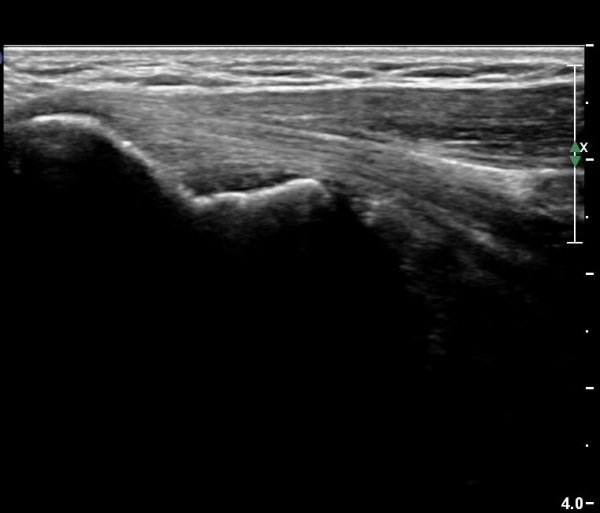

¼ÒµÎ Á¾´Ü¸é°Ë»ç¿¡¼­ ¼ÒµÎ¿Í ¿ä°ñµÎ Àü¹æ¿¡ ¼ö¾×Àú·ù°¡ °üÂûµÊ(»çÁø 3, 4).

ÁÖµÎ¿Í Á¾´Ü¸é°Ë»ç¿Í Ⱦ´Ü¸é°Ë»ç¿¡¼­ ÁֵοͿ¡ ÀÌÁúÀû¿¡ÄÚ¸¦ º¸ÀÌ´Â

´Ù·®ÀÇ ¼ö¾×Àú·ù°¡ °üÂûµÊ(»çÁø 5, 6).